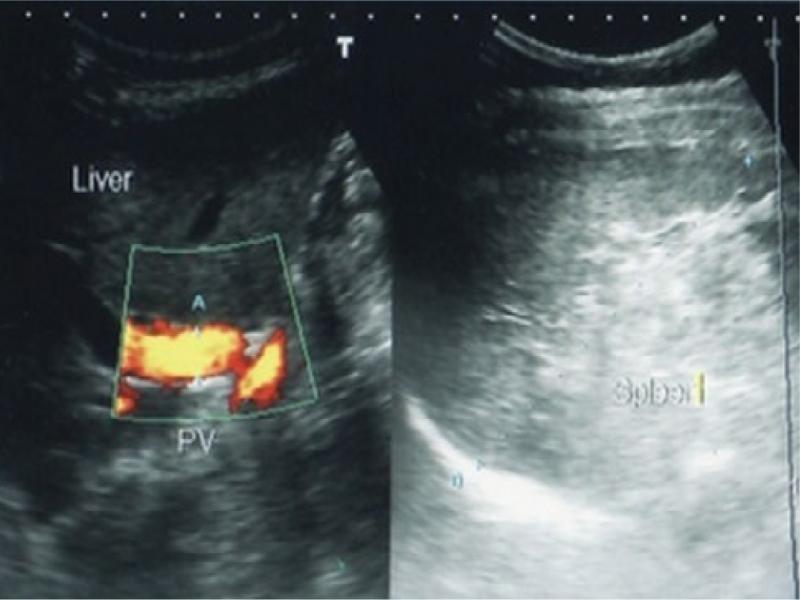

Fig. 2.